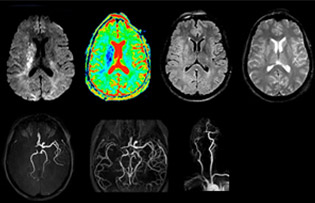

The first challenge in MRI of stroke is speed. The patient typically arrives from an ambulance in the MRI preparation room and the installation is done on a separate dock outside the scanner room. “The venous access is placed during the neurological examination. If the delay from the first symptoms allows the patient to receive thrombolysis we do a very fast examination that typically lasts about 11 minutes including the pre-scans. In the case of transient ischemic stroke we usually add ASL perfusion because in some symptoms with negative diffusion, ASL sometimes indicates a vascular origin.”

“Ingenia provides great flexibility in the parameters setting. We can tune a sequence the way we want,” says Dr. Savatovsky. “For example, in a stroke exam we use a FLAIR sequence of about two minutes instead of the four-minute FLAIR we use for MS. The diffusion is 30 seconds, the T2*-weighted scan is 30 seconds, the angiography scan time is less than one minute. Ingenia is a great scanner in that situation; even with these fast sequences we can achieve good images with good SNR. When the first sequence tells us that it’s not an ischemic stroke but a hemorrhagic stroke, we may switch to a time-resolved angiography to look for vascular malformations and venous thrombosis.

“Every center is different, but for me the ideal protocol for stroke includes diffusion weighted imaging, FLAIR, and fast susceptibility imaging,” says Dr. Savatovsky. “Our fast susceptibility weighted imaging takes 50 seconds, so it’s as fast as T2*-weighted imaging. It visualizes hemorrhage but also the clots. We also do 3D MR angiography that provides information on cervical and brain vessels. If the patient does not need immediate treatment, or if additional information is needed to decide on treatment, we might also add perfusion imaging and post-contrast T1-weighted imaging.”